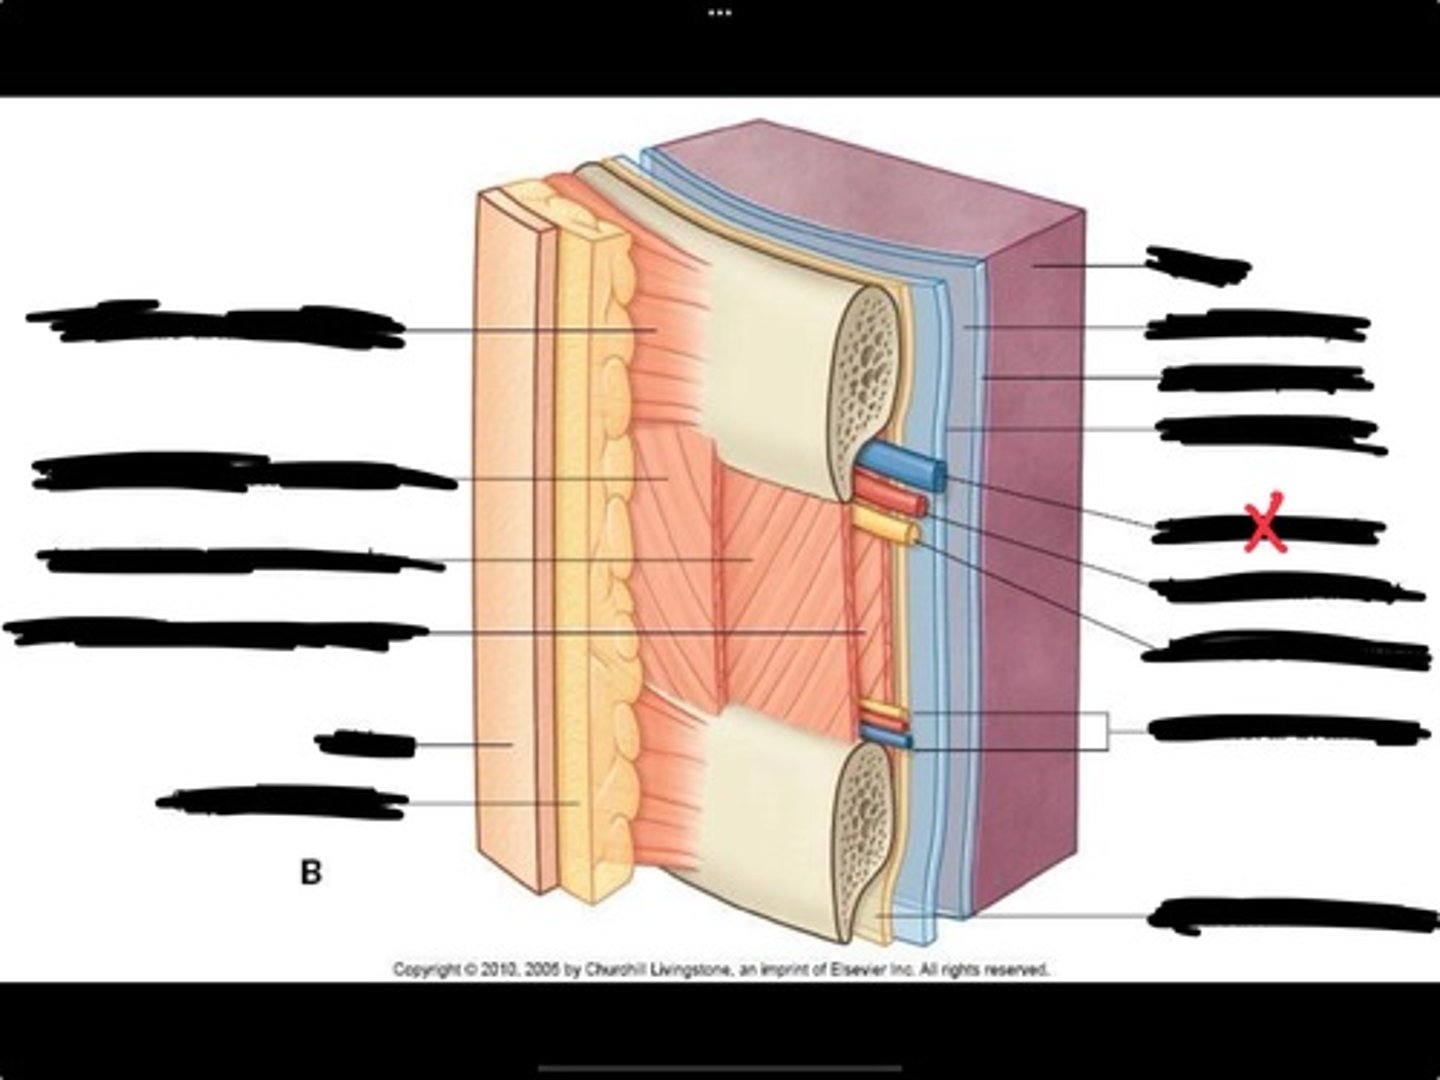

Innermost intercostal muscle

Skin

Internal intercostal muscle

External intercostal muscle

Serratus anterior muscle

Lung

Pleural cavity

Visceral pleura

Parietal cavity

Intercostal vein

Intercostal artery

Collateral branches

Intercostal nerve

Endothoracic fascia